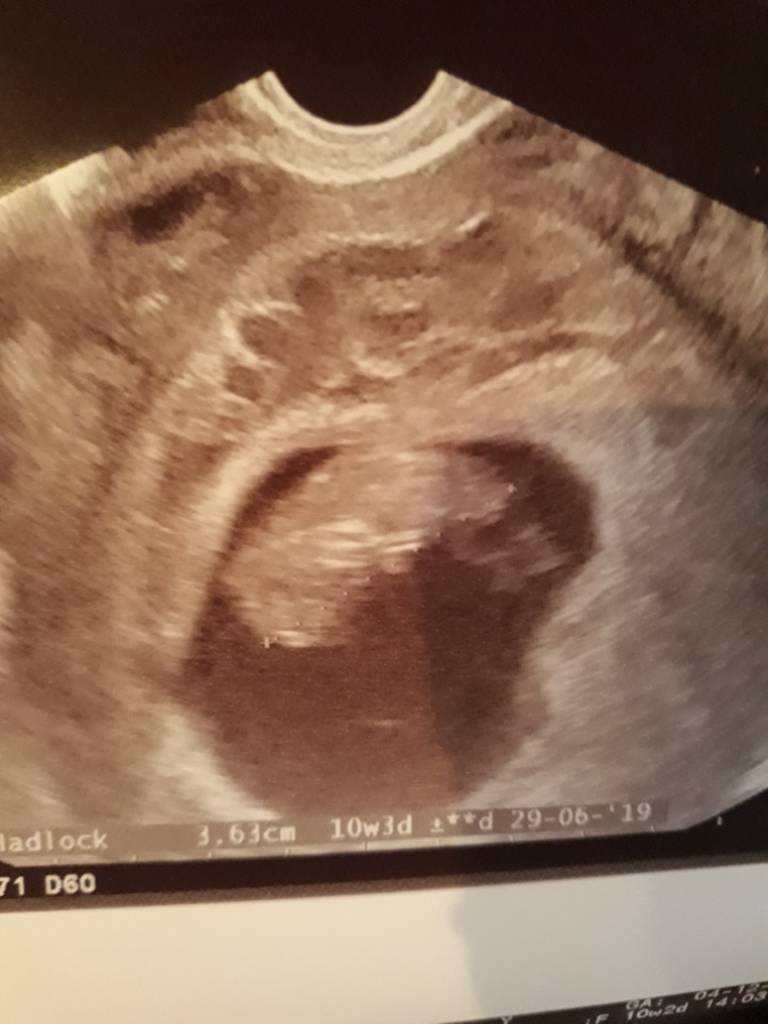

Przedstawiam Wam moje Kabanoski - tak je ochrzcilam, bo po kilku latach bezmiesnych musialam w tej ciazy zjesc kabanosy , bo bym oszalala !

Niestety krwiaki nadal sa